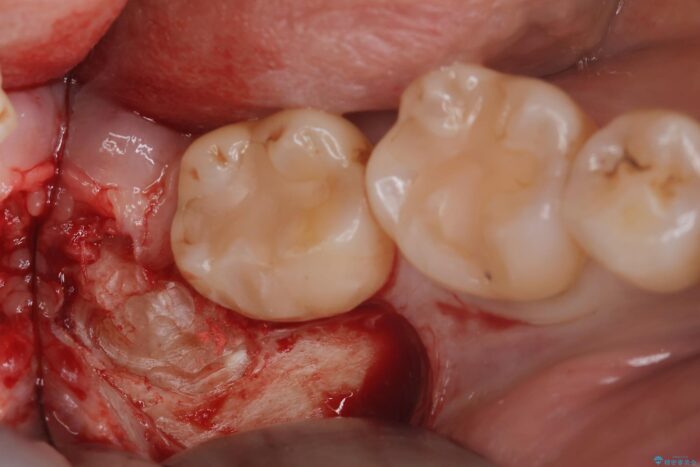

埋伏歯の抜歯

当日の抜歯も可能で、抜歯後1週間後に抜糸と消毒を行い処置は完了になります。

親知らずは虫歯のリスクが高いため抜歯をすることをお勧めします。